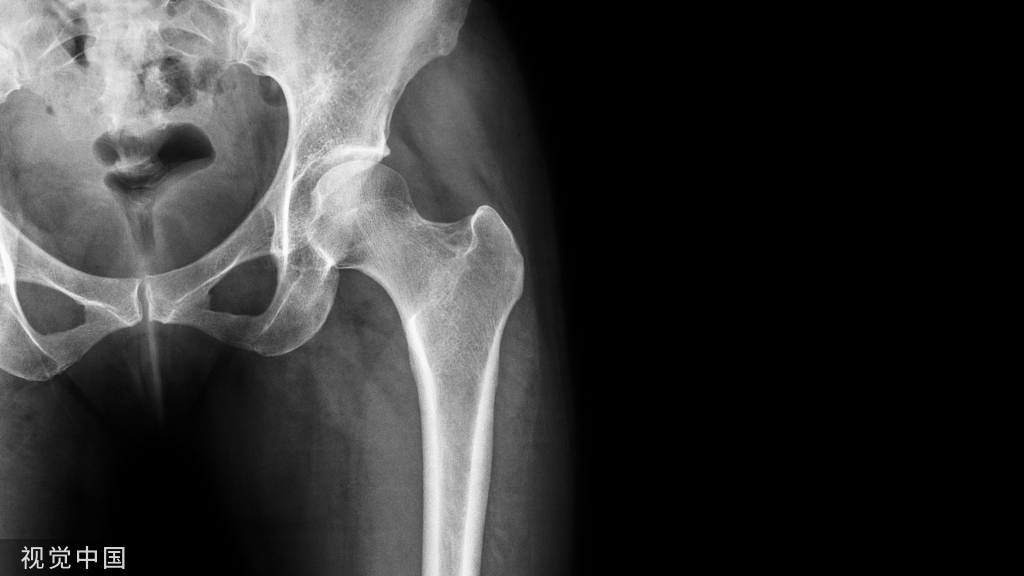

髋部骨折

一、髋部骨折患者术前翻身方法:

两人翻身法:1、操作者分别站在病人患侧的床边,先将病人的双手放于胸前,让病人屈曲健侧膝关节,操作者一人双手分别放至病人的肩和腰部,另一人将双手分别放至病人患肢的膝部小腿维持轴线牵引,先让病人健侧下肢配合用力,同时将身体抬起移向患侧床沿。

2、让病人稍屈曲健侧膝关节,在两膝间放置2-3个枕头,高度以病人双侧的髂前上棘之间的距离再加上5厘米,操作者一人双手分别放至病人的肩和腰部,另一人维持患肢轴向牵引力,两人同时将病人翻向健侧,将患肢置于两膝间的枕头上,保持患肢呈外展15度、髋膝伸直位牵引,然后在病人的背部垫软枕,胸前放一软枕放置上肢。

二、髋部骨折术后患者翻身方法:

两人翻身法:1、操作者分别站在病人患侧的床边,先将病人的双手放于胸前,让病人屈曲健侧膝关节,操作者一人双手分别放至病人的肩和腰部,另一人将双手分别放至病人的臀部和患肢膝部,并让病人健侧下肢配合用力,同时将身体抬起移向患侧床沿。

2、让病人稍屈曲健侧膝关节,在两膝间放置2-3个枕头,高度以病人双侧的髂前上棘之间的距离再加上5厘米,操作者一人双手分别放至病人的肩和腰部,另一人双手分别放置臀部和患肢膝部同时将病人翻向健侧,将患肢置于两膝间的枕头上,保持患肢呈外展15-20度、屈髋10-20度、屈膝45度,然后在病人的背部垫一软枕,胸前放一软枕放置上肢。

三、全髋关节置换术后 (THR)病人翻身方法: